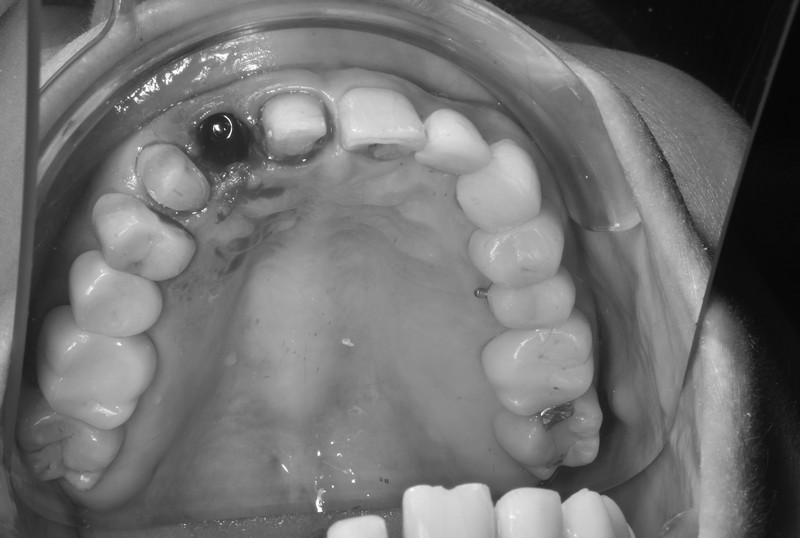

立即式植牙(即拔即種)

拔除牙齒的時候同時植入人工牙根,減少手術次數與等待時間,快速恢復咀嚼與外觀,縮短療程並降低不適感,適合即將拔除壞牙需植牙之患者。